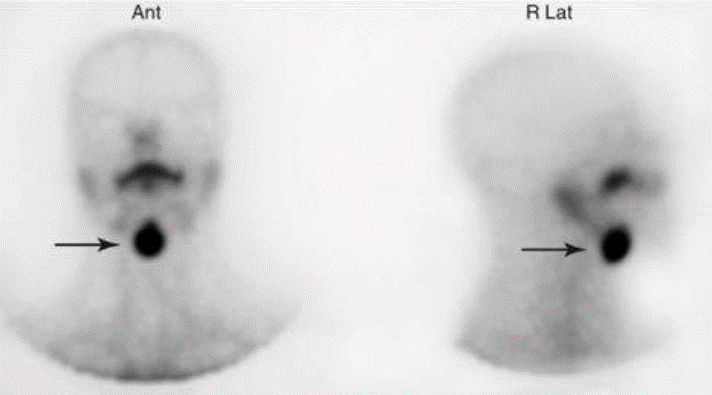

Sobre o estudo com pertecnetato-99mTc abaixo, assinale a alternativa correta.